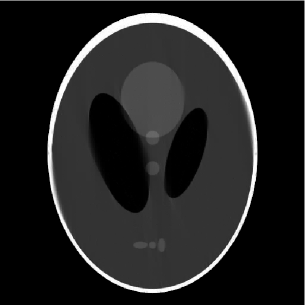

Figure 2: (a) 155155155 limited-angle projections in the 2-D frequency plane, (b) the full and outer-shell masks of the Shepp-Logan phantom, (c) FBP (PSNR=19.9PSNR19.9\mbox{PSNR}=19.9 dB), (d) DORE (PSNR=22.7PSNR22.7\mbox{PSNR}=22.7 dB), (e) GPSR (PSNR=22.9PSNR22.9\mbox{PSNR}=22.9 dB), (f) FPCASAS{}_{\footnotesize\mbox{AS}} (PSNR=22.5PSNR22.5\mbox{PSNR}=22.5 dB), (g) mask DORE (PSNR=25.8PSNR25.8\mbox{PSNR}=25.8 dB), (h) mask GPSR (PSNR=25.3PSNR25.3\mbox{PSNR}=25.3 dB), and (i) mask FPCASAS{}_{\footnotesize\mbox{AS}} (PSNR=26.4PSNR26.4\mbox{PSNR}=26.4 dB) reconstructions.

Shepp-Logan phantom reconstruction. We simulated limited-angle parallel-beam projections of an analog Shepp-Logan phantom with 1superscript11^{\circ} spacing between projections and missing angle span of 25superscript2525^{\circ}. Each projection is computed from its analytical sinogram using [8, function ellipse_sino.m] and [7] and then sampled by a receiver array containing 511511511 elements. We then compute FFT of each projection, yielding N=512𝑁512N=512 frequency-domain measurements; the corresponding frequency-domain sampling pattern is shown in Fig. 2.

Fig. 2 depicts both the full and outer-shell masks of the phantom that we use to implement the DORE, GPSR, FPCASAS{}_{\footnotesize\mbox{AS}} and mask DORE, GPSR, and FPCASAS{}_{\footnotesize\mbox{AS}} methods, respectively. Because of the nature of X-ray CT measurements, our full mask has circular shape containing p=205859𝑝205859p=205859 signal elements. The elliptical outer-shell mask containing pM=1308150.6355psubscript𝑝M1308150.6355𝑝p_{{\scriptstyle{\rm M}}}=130815\approx 0.6355\,p pixels has been constructed from the phantom’s sinogram using k=1180Aπ(k1)/180superscriptsubscript𝑘1180subscript𝐴𝜋𝑘1180\bigcap_{k=1}^{180}A_{\pi\,(k-1)/180}, see Section V; this choice of the mask implies that we have prior information about the shape of the outer shell of the Shepp-Logan phantom beyond the information available from the limited-angle projections that we use for reconstruction, see Fig. 2.

Figs. 22 show the reconstructions of various methods. To facilitate comparison, we employ the common gray scale to represent the pixel values within the images in Figs. 22. Clearly, taking the object’s contour into account improves the signal reconstruction performance.